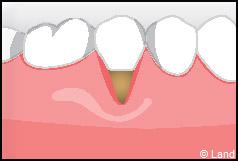

LES TECHNIQUES AVEC APPORT DE GENCIVE OU « GREFFE DE GENCIVE » :

Elles font appel à un prélèvement sur le patient à un endroit où elle est en excès, qui est ensuite posé sur la récession.

Il y a 2 types de « greffes » de gencives :

Les greffes épithélio-conjonctives :

Elles sont pratiquées pour des zones non esthétiques de la cavité buccale, à cause de l’aspect « rustine» que la cicatrisation leur confère.

Destinées aux zones esthétiques, elles consistent à prélever la partie profonde du palais (site donneur).